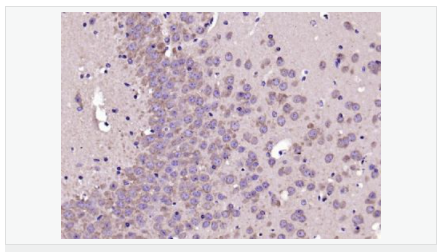

| 產(chǎn)品應(yīng)用 | ELISA=1:5000-10000 IHC-P=1:100-500 IHC-F=1:100-500 IF=1:200-800 (石蠟切片需做抗原修復) not yet tested in other applications. optimal dilutions/concentrations should be determined by the end user. |

| 產(chǎn)品介紹 | This gene encodes a member of the corticotropin-releasing factor family. The encoded preproprotein is proteolytically processed to generate the mature neuropeptide hormone. In response to stress, this hormone is secreted by the paraventricular nucleus (PVN) of the hypothalamus, binds to corticotropin releasing hormone receptors and stimulates the release of adrenocorticotropic hormone from the pituitary gland. Marked reduction in this protein has been observed in association with Alzheimer's disease. Autosomal recessive hypothalamic corticotropin deficiency has multiple and potentially fatal metabolic consequences including hypoglycemia and hepatitis. In addition to production in the hypothalamus, this protein is also synthesized in peripheral tissues, such as T lymphocytes, and is highly expressed in the placenta. In the placenta it is a marker that determines the length of gestation and the timing of parturition and delivery. A rapid increase in circulating levels of the hormone occurs at the onset of parturition, suggesting that, in addition to its metabolic functions, this protein may act as a trigger for parturition. [provided by RefSeq, Nov 2015] Function: This hormone from hypothalamus regulates the release of corticotropin from pituitary gland. Subunit: Interacts (via C-terminus) with CRFR1 (via N-terminal extracellular domain). Subcellular Location: Secreted. Similarity: Belongs to the sauvagine/corticotropin-releasing factor/urotensin I family. SWISS: P06850 Gene ID: 1392 Database links: Entrez Gene: 1392 Human Entrez Gene: 12918 Mouse Omim: 122560 Human SwissProt: P06850 Human SwissProt: Q8CIT0 Mouse Unigene: 75294 Human Unigene: 290689 Mouse Unigene: 10349 Rat Important Note: This product as supplied is intended for research use only, not for use in human, therapeutic or diagnostic applications. CRF陽性神經(jīng)元的胞體廣泛分布于下丘腦的室旁核、背縫核和藍斑核,這些區(qū)域也是去甲腎上腺素(NE)神經(jīng)元與5-羥色胺(5-HT)神經(jīng)元密集的區(qū)域。 CRF既具有神經(jīng)遞質(zhì)的性質(zhì)又具有神經(jīng)激素的性質(zhì)。CRF是聯(lián)系神經(jīng)系統(tǒng)與內(nèi)分泌系統(tǒng)的橋梁,在情感障礙疾患如焦慮和抑郁的發(fā)病中發(fā)揮重要作用. |